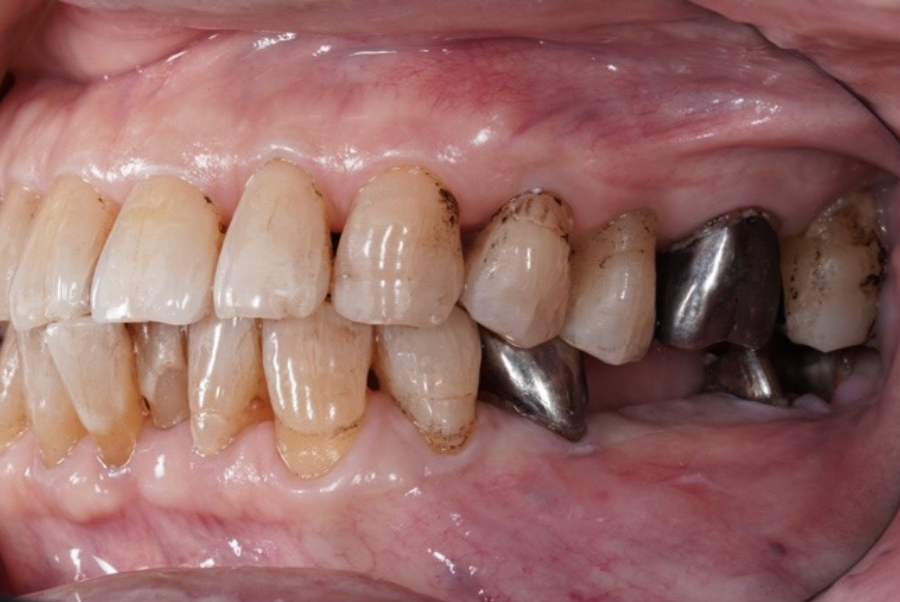

【治療前の状態(Before)】

左下のブリッジ支台歯に歯根破折が認められ、保存は困難な状態でした。

噛んだ際の違和感があり、奥歯としての機能が十分に果たせていませんでした。